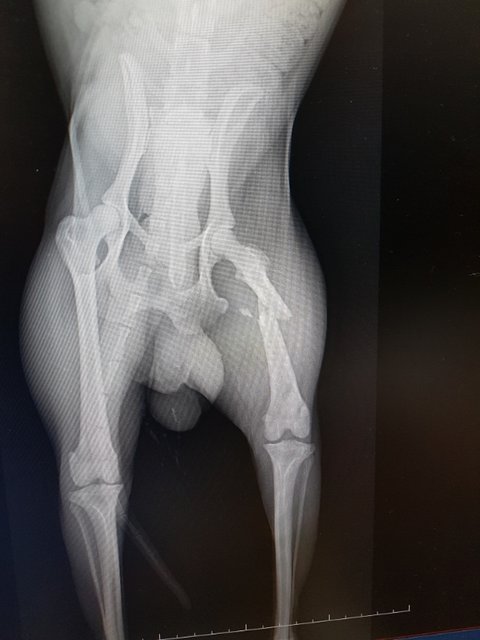

엑스레이 결과 대퇴부가 골절되었습니다.

불행중 다행인지 다른곳 골절은 보이지 않는다고 합니다